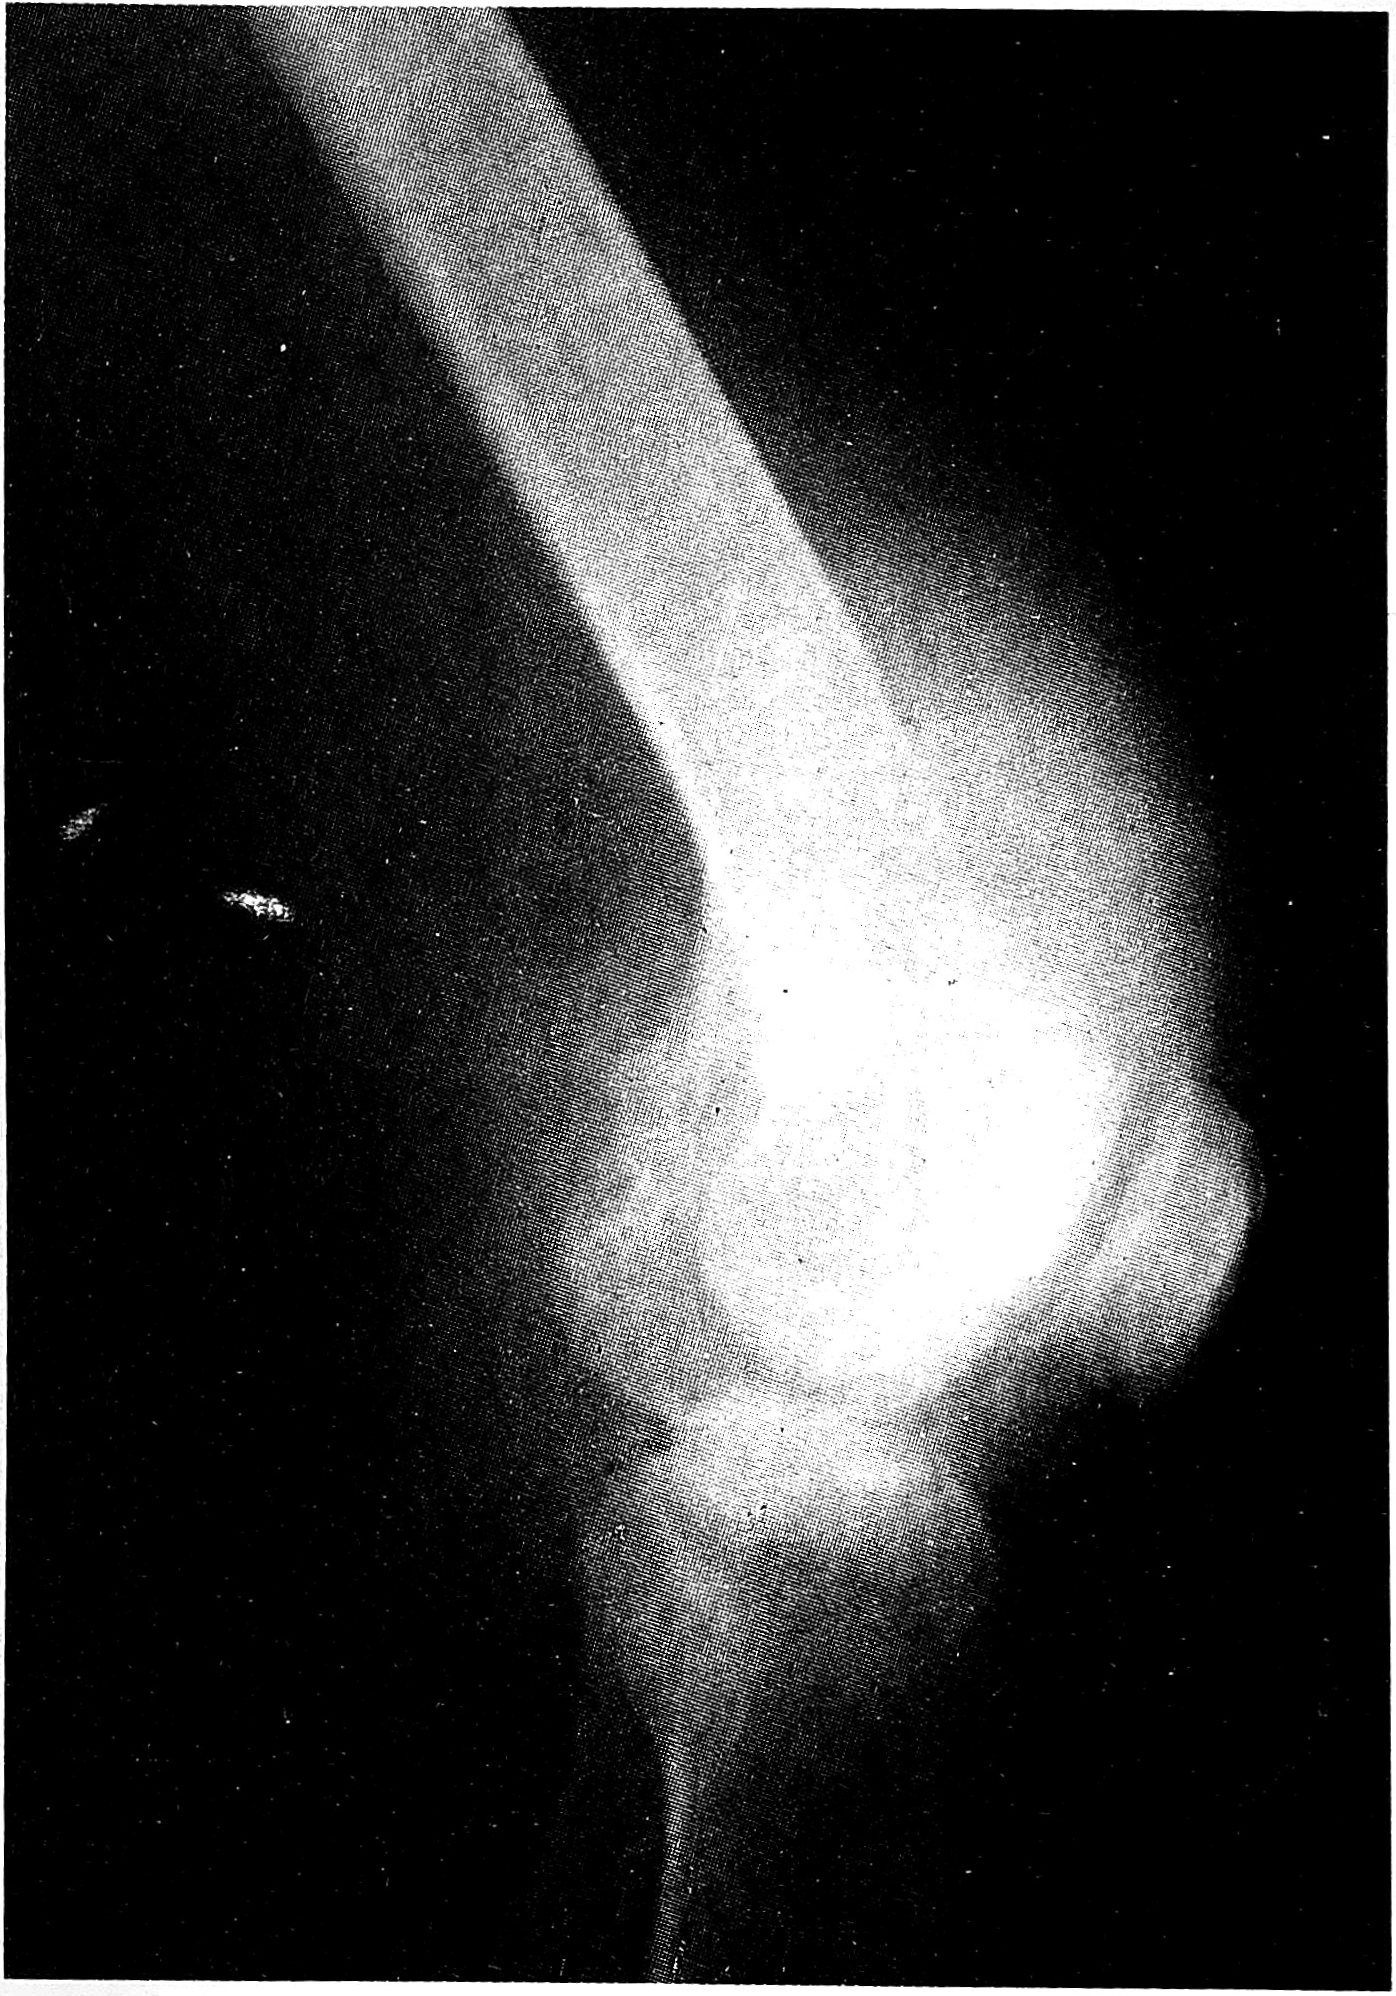

4.10.92 произведена вторая операция — остеотомия на двух уровнях: в верхней трети бедра и в проксимальном отделе голени. Наложен штифтовой аппарат внешней фиксации и через 2 нед начата дистракция по 1 мм в сутки на двух уровнях. Peгенераты формировались на обоих уровнях. Постепенно у больной развилась эквинусная деформация стопы. 28.09.93 выполнена закрытая ахиллотомия. Через 14 мес достигнуто удлинение конечности на 21 см (14 см на бедре и 7 см на голени). На обоих уровнях сформировались регенераты (см. рис. 3 на вклейке). Аппарат снят и наложена кокситная гипсовая повязка на 2 мес для уплотнения регенератов.

Рис. 3. Рентгенограммы той же больной после остеотомии бедренной кости (а) и костей голени (б) и дистракции в аппарате внешней фиксации. Виден регенерат.

Через 2 года после начала комбинированного лечения у больной нет признаков рецидива и отдаленных метастазов. Достигнуто уравнивание длины конечностей, неврологических расстройств нет. Чувствительность и движения в стопе сохранены в полном объеме.